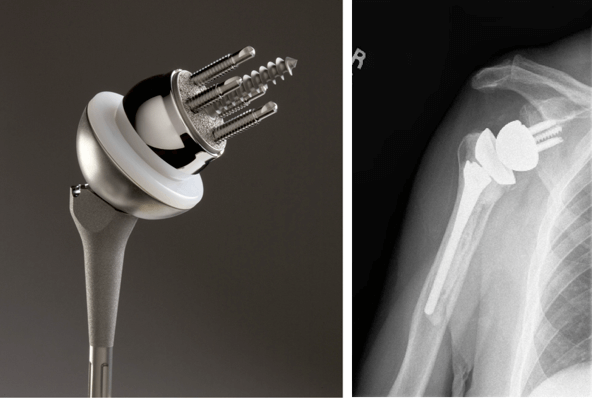

- Полное. При этом меняются все соприкасающиеся части: и головка, и впадина. Причем возможны два варианта замены: имплантируются только суставные элементы или производится установка протезов на стержне с креплением в костной полости.

Имплантаты на ножке по своему строению могут быть анатомическими и обратными. Анатомический состоит из трех частей: головка, ножка и впадина. Назван так, поскольку полностью повторяет структуру человеческого плеча и по биомеханике, и по форме.

Установка такого протеза возможна только в том случае, если вращательная манжета не повреждена. При замене используется продукция таких мировых производителей как DePuy, Zimmer, Smith&Nephew, Biomet, Aesculap — B. Braun.

Обратный или реверсивный используется, когда вращательная манжета не функционирует и нарушена стабильность. Тогда головка крепится к суставной впадине (гленоидальному компоненту), а вогнутый имплантат впадины на ножке фиксируется на плечевой кости.